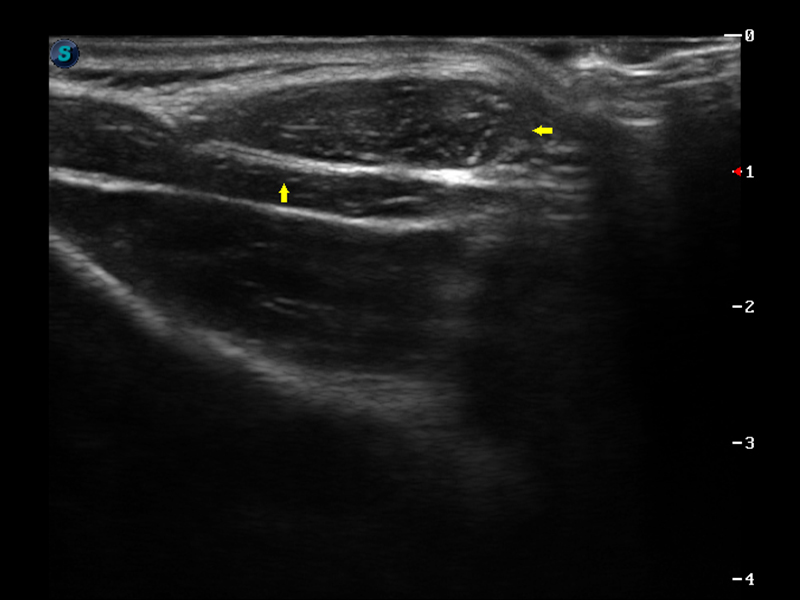

μ-Scan微米成像

实时宽景成像